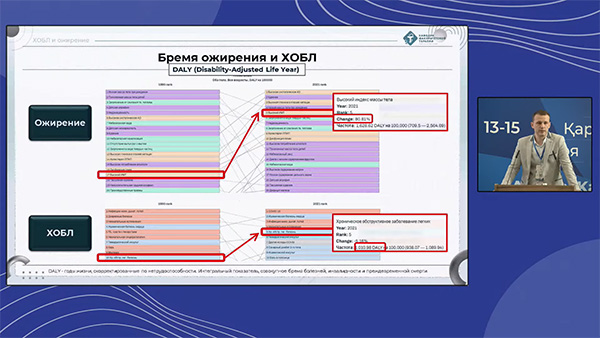

Юрий Панфилов выступил с докладом «ХОБЛ и ожирение: от патофизиологического парадокса к тактике ведения пациентов», представив актуальные данные и клинические рекомендации для ведения пациентов с сочетанной патологией.